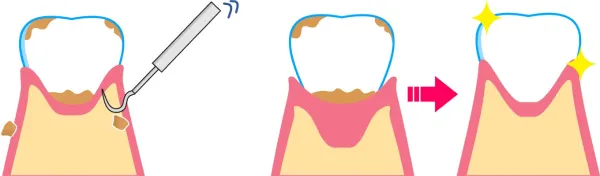

歯石取り

磨きにくい環境を改善するため、歯科衛生士による根の周りにこびりついた石灰化物の除去「歯石取り」を行います。これによって、根の表面を滑沢にして、汚れを落としやすくします。 ここまでの治療で効果が及ばないところは、検査によって出血します。この環境では炎症が引かないということになるので、場合によっては手術に移行していきます。

コントロールできた状態とは

歯周病治療を行った結果、炎症がコントロールされた状態とは、炎症がなくなり(歯肉からの出血がなくなり)、最近との共生関係が確立(細菌がいなくなるのではなく影響がなくなる)その環境が永続しやすいような状態(浅いポケット)になることです。 残念ながらそれは、以前のように歯の間が歯肉に満たされ、骨が上まである状態ではありません。吸収してしまった骨は基本的には元には戻らず、歯肉は下がった状態で安定します。図に書くと以下のようになります。

骨は歯肉の中で吸収し、歯肉の中と外には歯石と歯垢がこびりつき、それに伴い歯肉は腫れあがっています。 この状態に対し、患者さんのブラッシングが解消、歯科医院側では歯石取りとみがき残した部分のクリーニング、場合によっては手術を行って磨きやすい環境に変えてそれを持続すると…。

治療によりコントロールできた状態

歯周病の状態に対し、患者さんのブラッシングが解消、歯科医院側では歯石取りとみがき残した部分のクリーニング、場合によっては手術を行って磨きやすい環境に変えてそれを持続すると、このように変わります。 つまり、歯肉は腫れがなくなり、溶け続けていた骨は安定して固まり、骨の2~3ミリ上に歯肉が炎症が無い状態です。残念ながら、骨も歯肉も増殖せず、元の位置に回復とはいきません。これが歯周病からの治癒像です。 事故で手や足がなくなった人が再生しないのと同じように、これが現在の限界なのです。